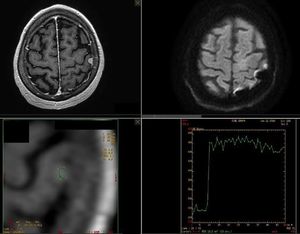

Multiparametric brain MR Imaging for meningioma evaluation. High resolution anatomical sequences, DWI with b0, b500, b1000 and ADC map, and DCE PWI were obtained. Images courtesy of Christos Tsiotsios.